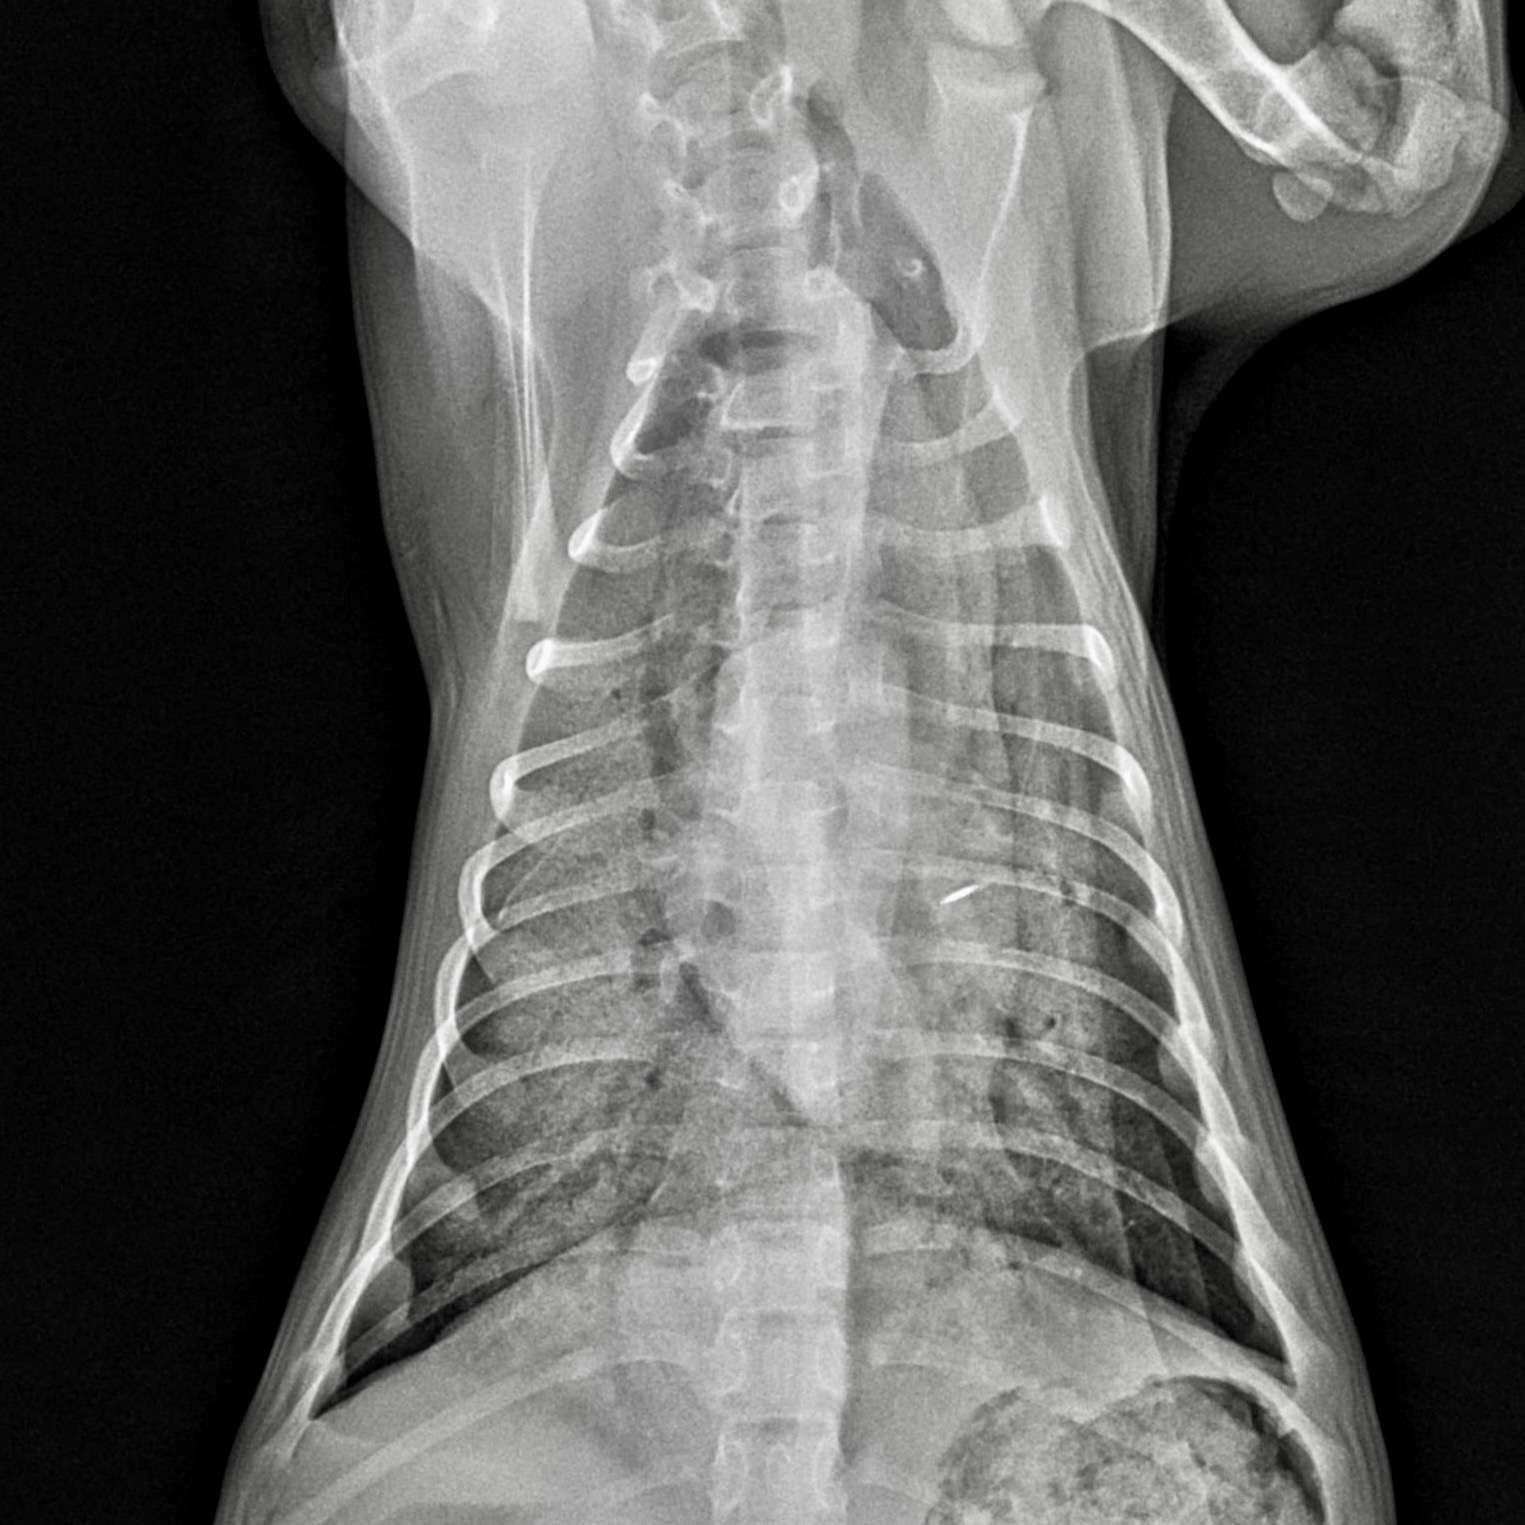

Thoracic radiography

Radiographs typically show:

- Interstitial to alveolar infiltrates

- Perihilar or caudodorsal distribution (variable)

- Normal cardiac silhouette in most cases

Radiographs help confirm pulmonary edema and identify aspiration or traumatic injury.